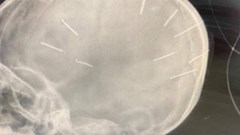

VHO - Sở Y tế tỉnh Thanh Hoá vừa có văn hoả tốc gửi các đơn vị y tế trong tỉnh, UBND huyện Mường Lát và các đơn vị liên quan tăng cường triển khai các biện pháp phòng, chống bệnh bạch hầu theo lĩnh vực, địa bàn quản lý.